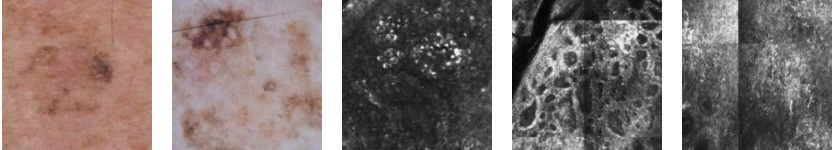

Dermoscopy showed atypical network with grey dots and granules. Structures were predominant at the periphery with structureless areas in the center. Confocal microscopy demonstrated atypical cobblestone pattern in the epidermis with pagetoid cells. Loss of typical meshwork pattern in the dermal-epidermal junction. Bright cells infiltrating the rete and numerous spindle shaped structures. Clinical differential diagnosis included melanoma on sun-damaged skin or evolving melanoma in-situ.